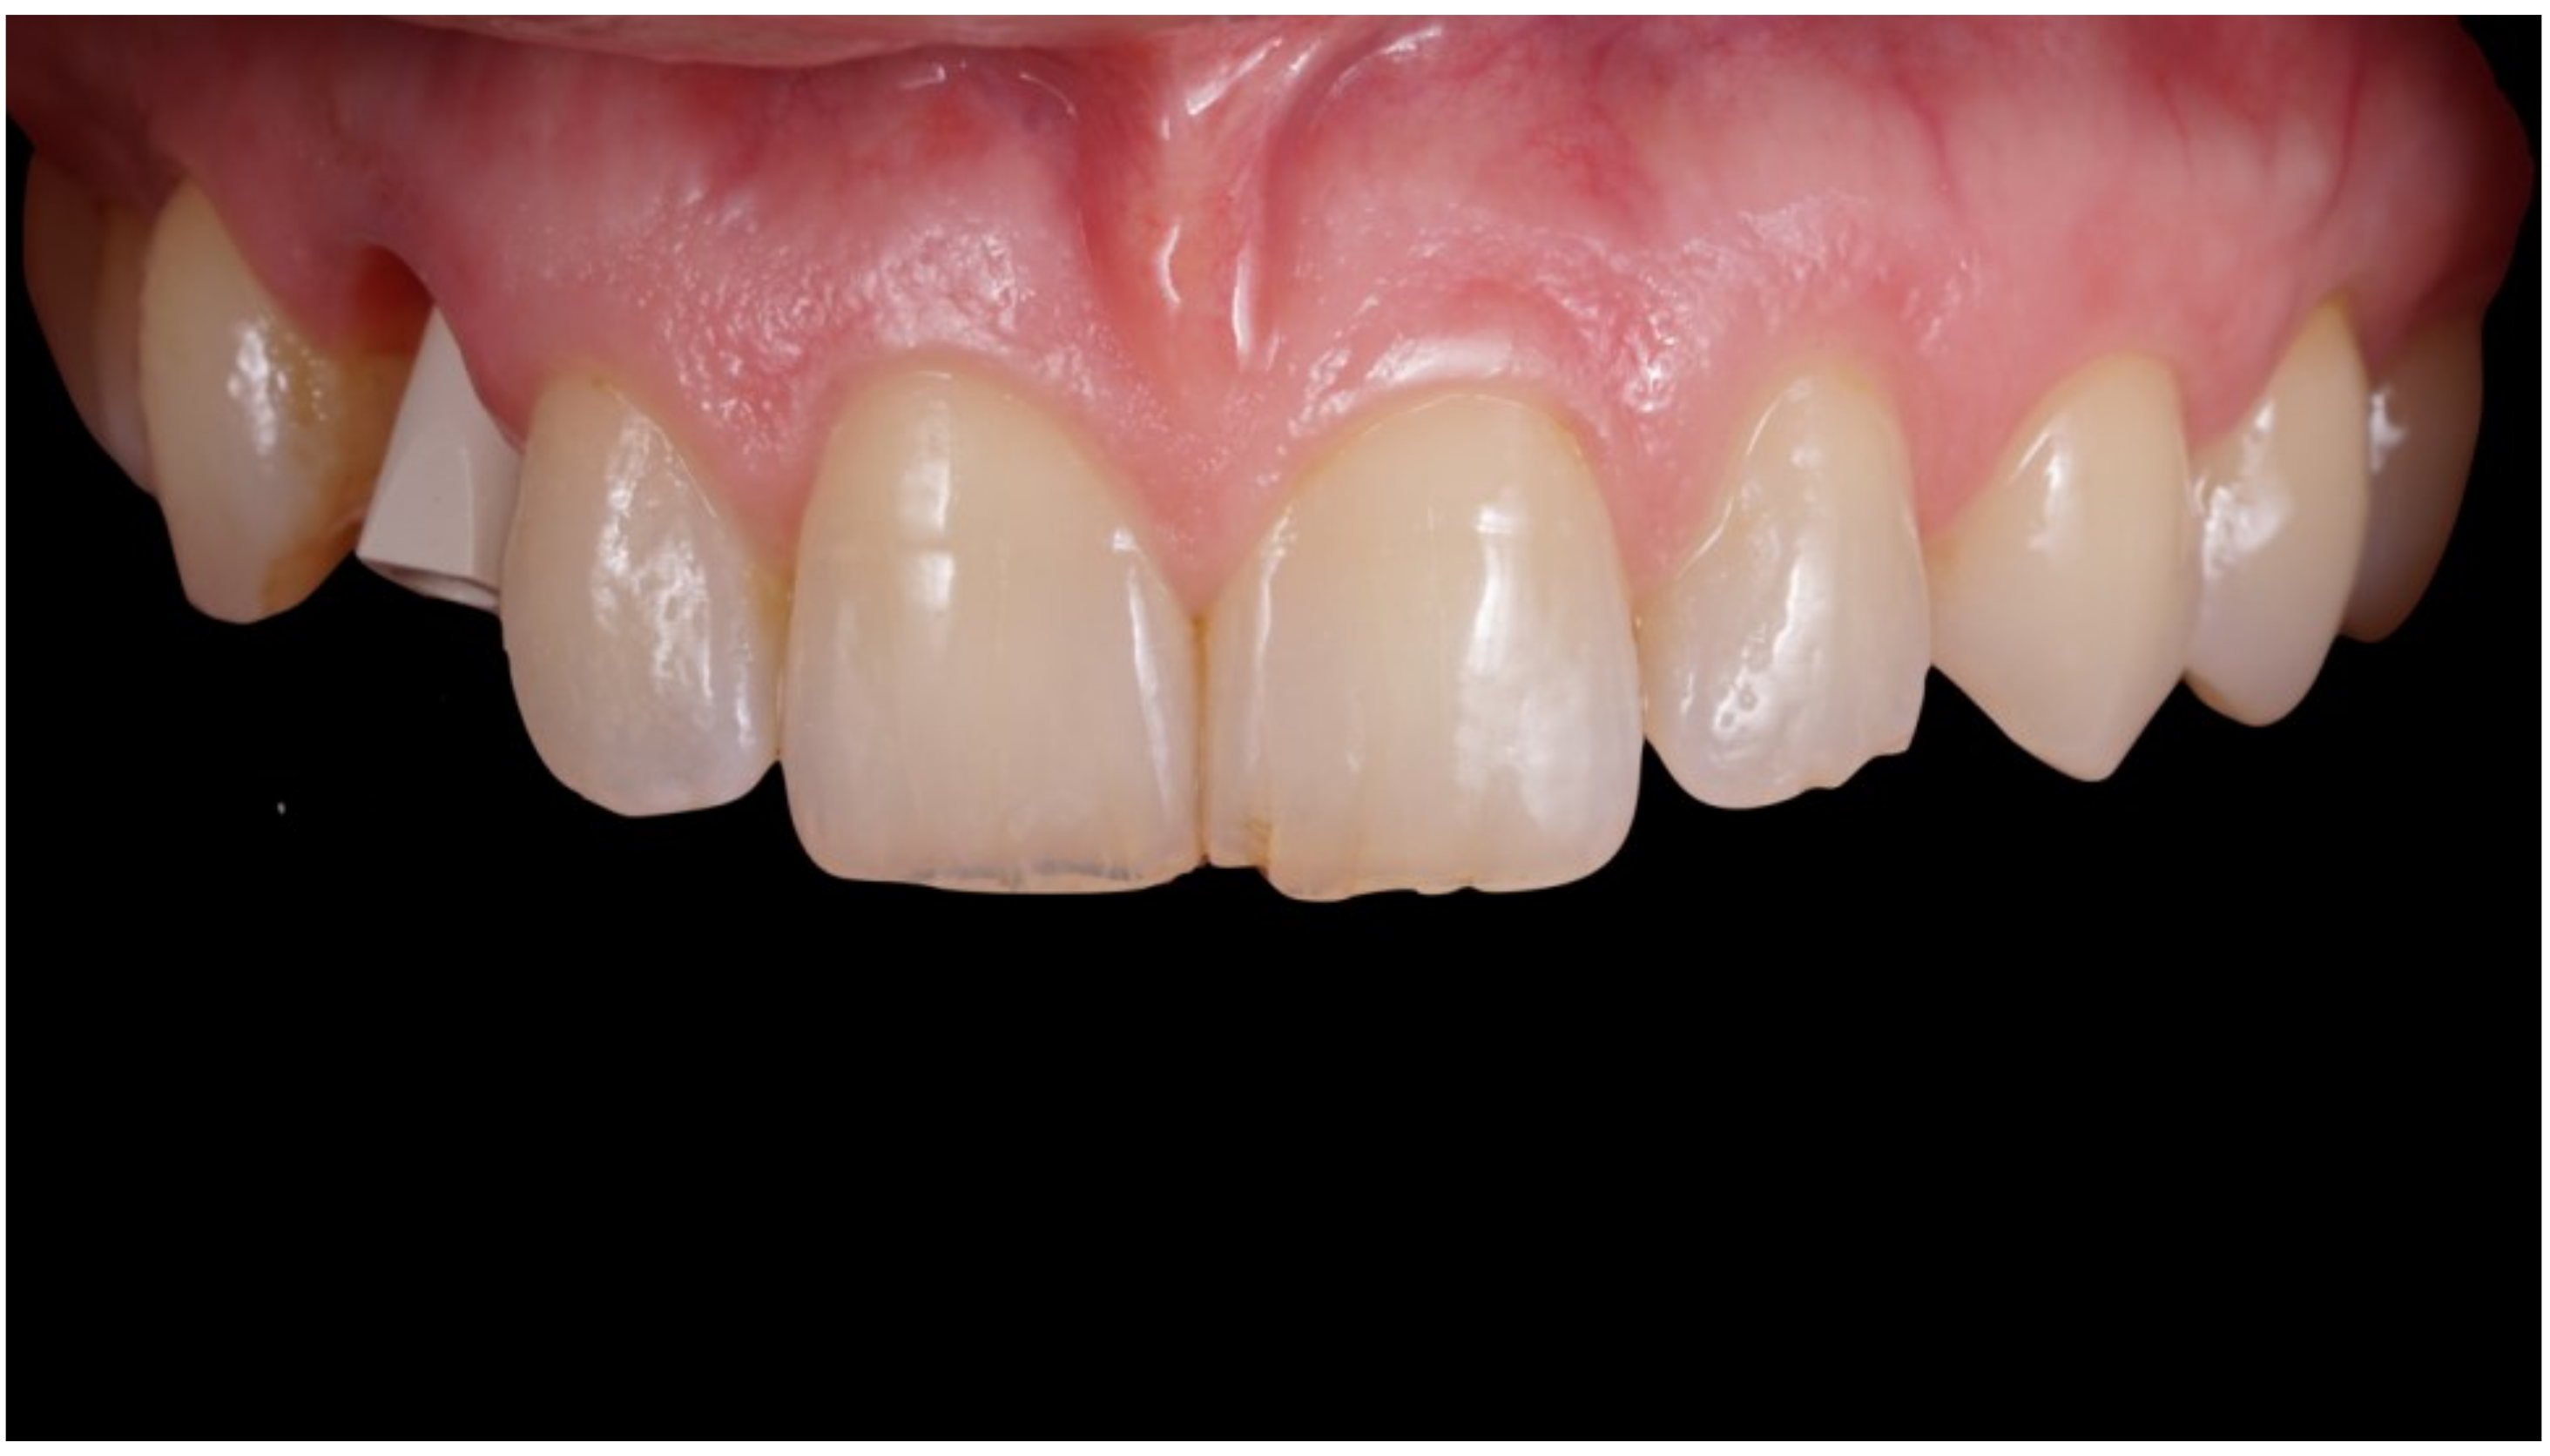

Figure 8.

Delivery of final crown.

Figure 9.

Definitive crown after 1 year of follow-up, frontal view.